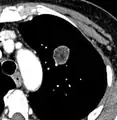

Spiculated lung nodule.[9]

- Margin morphology: a spiculated margin is a risk factor for cancer.[8] Benign causes tend to have a well defined border, whereas lobulated lesions or those with an irregular margin extending into the neighbouring tissue tend to be malignant.[10] In particular, spiculations are highly predictive of malignancy with a positive predictive value up to 90%.[9] Also, a "notch sign", which is an abrupt indentation of the nodule, increases the risk of cancer, but may also be found in granulomatous diseases.[9]